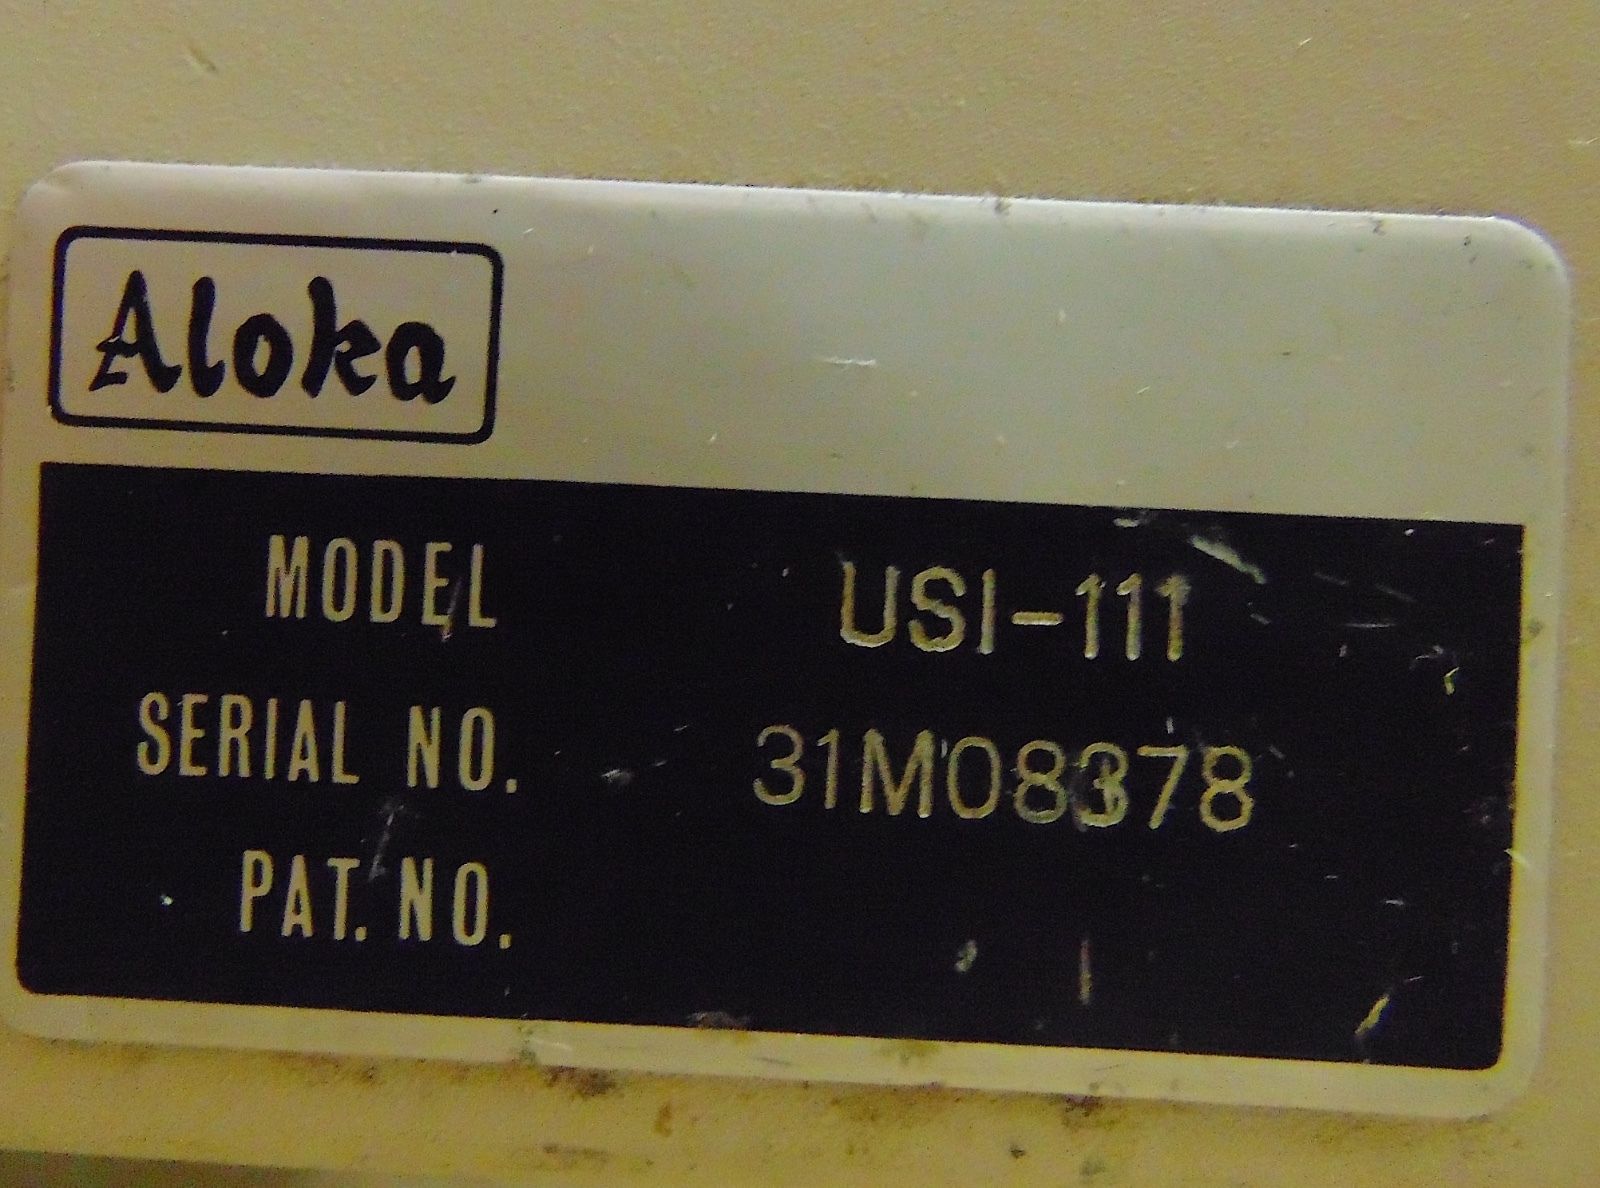

Brand: Aloka

MPN: 31M08378

Model: SSD-620